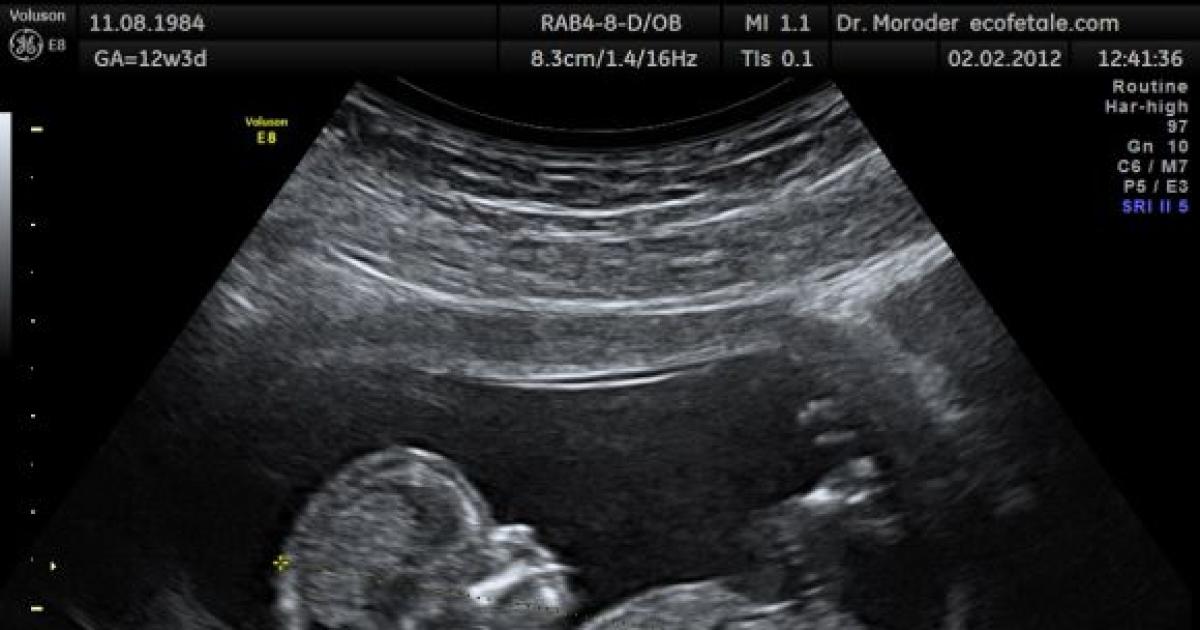

Both the baby and the mother were given local anaesthesia. The baby was also given a muscle relaxant so it wouldn't switch positions at an inopportune time. Doctors performing the surgery at CHA Hollywood Presbyterian Medical Centre relied on ultrasound imaging to see what they were doing.